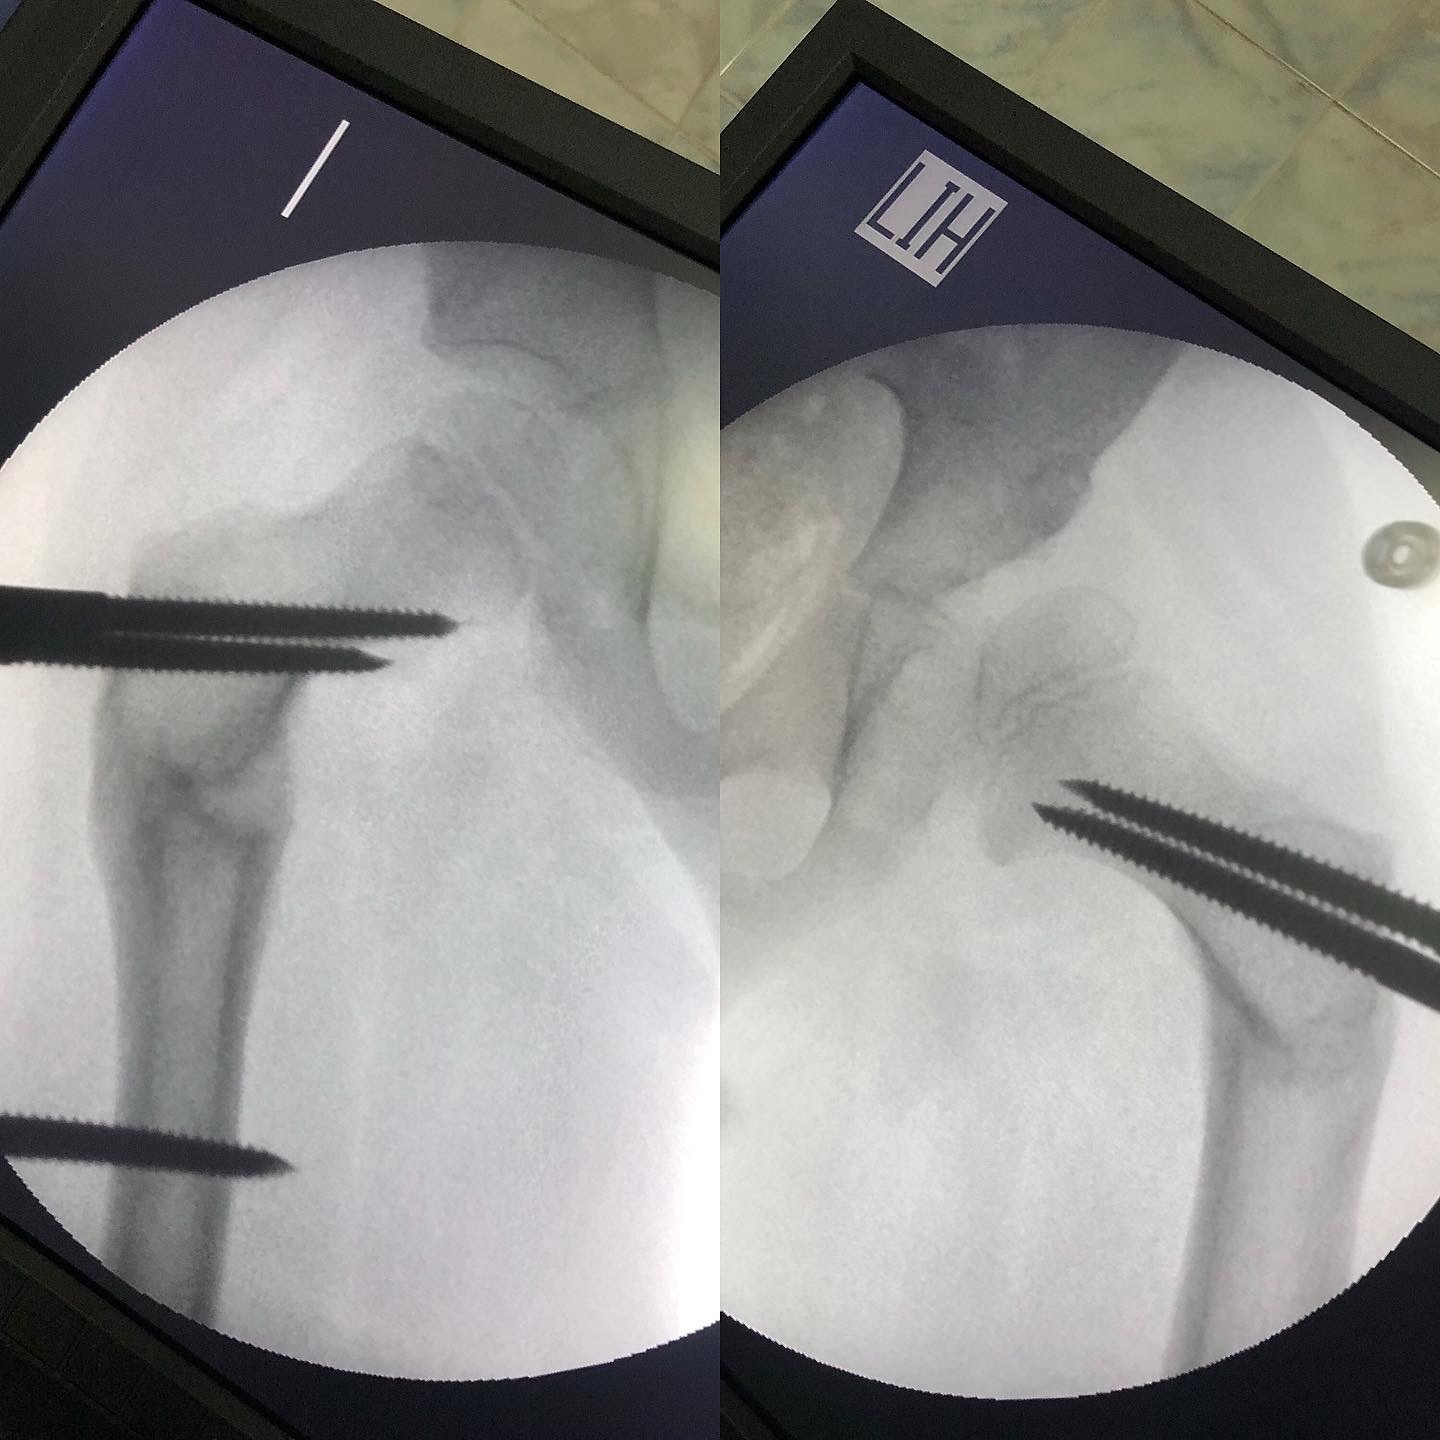

Диагноз: Дисплазия обеих тазобедренных суставов. Маргинальный вывих правого тазобедренного сустава. Укорочение правого бедра на 2 см.

Выполнено: операция по коррекции шеечно-диафизарных углов с одновременным удлинением правого бедра на 2 см.

Фиксация АВФ без разрезов кожи (с проколов).